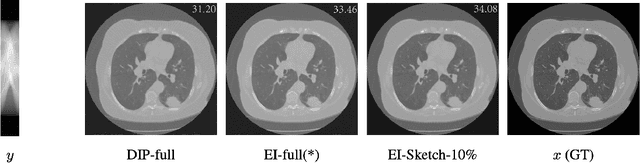

Abstract:Equivariant Imaging (EI) regularization has become the de-facto technique for unsupervised training of deep imaging networks, without any need of ground-truth data. Observing that the EI-based unsupervised training paradigm currently has significant computational redundancy leading to inefficiency in high-dimensional applications, we propose a sketched EI regularization which leverages the randomized sketching techniques for acceleration. We then extend our sketched EI regularization to develop an accelerated deep internal learning framework -- Sketched Equivariant Deep Image Prior (Sk.EI-DIP), which can be efficiently applied for single-image and task-adapted reconstruction. Our numerical study on X-ray CT image reconstruction tasks demonstrate that our approach can achieve order-of-magnitude computational acceleration over standard EI-based counterpart in single-input setting, and network adaptation at test time.